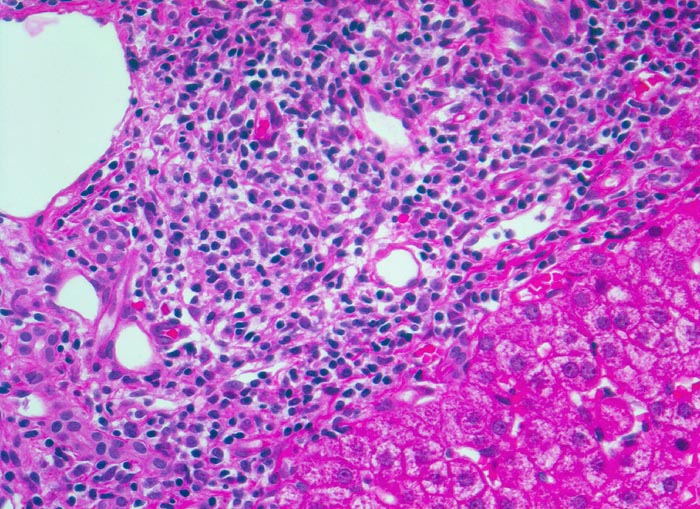

chronische Hepatitis C mit geringgradiger Aktivität

Links im Bild Portalfeld mit starker Vermehrung von Lymphozyten mit kleinen runden Kernen und Plasmazellen mit exzentrisch gelegenen Kernen und basophilem Zytoplasma mit perinukleärer Aufhellung.

Fibrose der Portalfelder mit portoportaler Septenbildung.

Intravenöser Drogenabusus vor 10 Jahren. Damals Infektion mit dem Hepatitis C Virus.